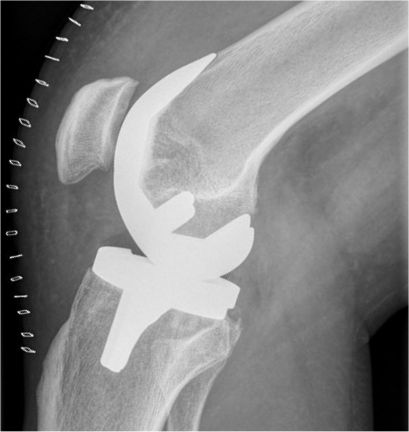

Bereits nach einer Woche wurde ich aus dem Krankenhaus entlassen und war dank Unterarmgehstützen schon sehr gut mobil. Kurze Strecken (z.B. im Haus) konnte ich auch ohne Gehhilfen bewältigen. Zur Linderung der natürlich noch vorhandenen Schmerzen wurde nur Tramadol 100 mg und Novaminsulfon 500 mg verordnet.

Willis neues Kniegelenk (rechts) – die Wundklammern sind gut sichtbar